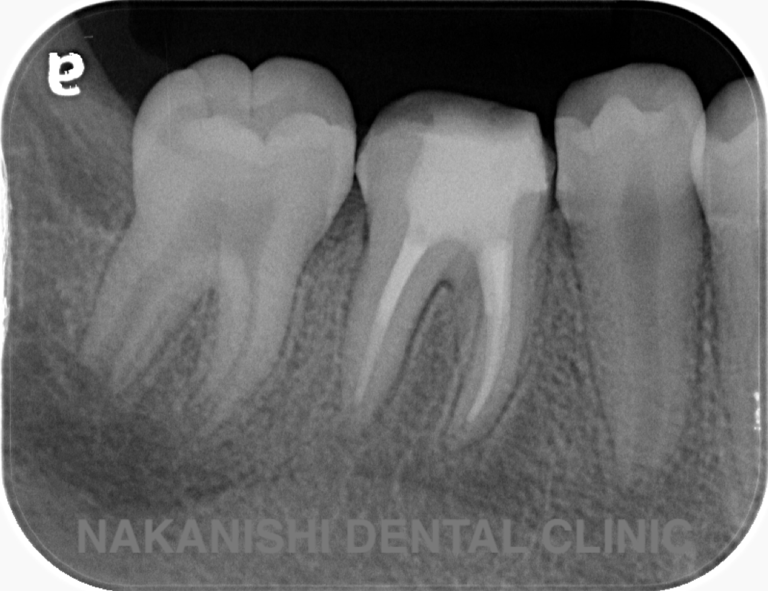

case 2.

治療前

治療後

| 主訴 | 左下歯ぐきの腫れ。 |

|---|---|

| 治療期間 | 約2か月 |

| 治療費 | 約1万5千円 |

| 治療内容 | ラバーダム、マイクロスコープ下にて根管治療を施術。 歯ぐきの腫れ、痛みや違和感が消失したため根管充填、支台築造(土台の製作)を行った。治療後の写真は矯正治療を行うことになったため仮歯を装着した状態。 |

| 治療のリスク | マイクロスコープやCTを使用し、可能な限り精密な根管治療を行っていますが、歯根の形態や病変の大きさ、過去の治療履歴などにより、治癒が得られない場合があります。また、治療後に再感染や歯根破折が生じることもあり、その場合は再治療や抜歯が必要となることがあります。 治療結果には個人差があり、すべての症例で同様の経過を保証するものではありません。 |